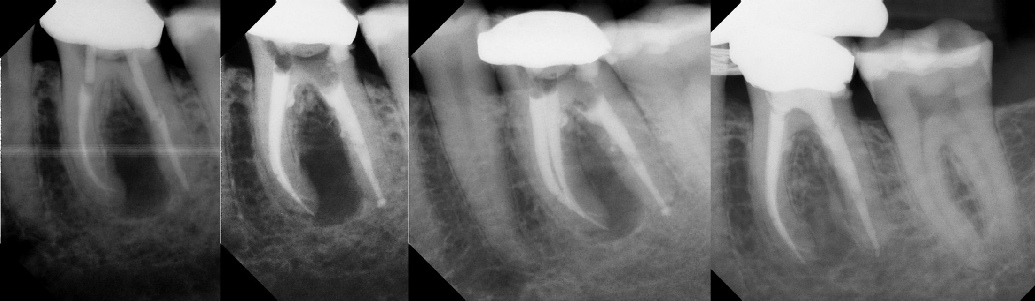

COMPLICATED ANATOMY LARGE LESIONS CALCIFIED CANALS PERFORATION / RESORPTION SEPARATED INSTRUMENTS SURGICAL CASES RETREATMENT / pOST REMOVAL OPEN APICES ACCESS THRU CROWNS Root Canal Case Portfolio

6 mos.